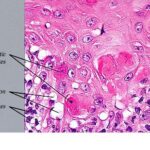

Histopathology. EM is considered the prototype of the vacuolar form of interface dermatitis . The early changes include vacuolization of the basal cell layer; tagging of lymphocytes along the dermal-epidermal junction; and a sparse, superficial, perivascular lymphoid infiltrate . Necrosis of individual keratinocytes in the basal unit occurs, which is the hallmark of EM. Because of its acute nature, there is an orthokeratotic stratum corneum. Mild spongiosis, papillary dermal edema, and extravasation of red blood cells are seen. As the lesion becomes more developed, there is a moderate lichenoid infiltrate of Iymphohistiocytes at the dermal-epidermal junction with exocytosis. More apoptotic keratinocytes within and above the basal epidermal layer are present. The |

intensity of epidermal necrosis varies from vacuolated individual keratinocytes surrounded by lymphocytes (satellite cell necrosis) at the basal unit to confluent necrosis in association with intraepidermal and subepidermal vesicles. The dermal infiltrate comprises lymphocytes and histiocytes. Eosinophils may also be present. Although one study has noted a significant number of eosinophils in drug-induced EM, this has not been noted by others. In the authors’ estimation, a generous number of eosinophils exclude EM. One study has found that an acrosyringium concentration of apoptotic keratinocytes in EM is a clue to a drug etiology . In early lesions of SJSITEN, apoptotic keratinocytes are observed scattered in the basal layer of the epidermis. In established lesions, there are numerous necrotic keratinocytes, even full-thickness epidermal necrosis, and a subepidermal bulla. The dermal inflammatory infiltrate is sparser in TEN than in EM (Fig. 9-278). Extravasated erythrocytes are commonly found within the blister cavity. Melanophages within the papillary dermis occur in late lesions. Eccrine epithelium shows a variety of changes from basal cell apoptosis to necrosis of the duct. |

In general, EM shows less epidermal necrosis, more dermal inflammation, and exocytosis, whereas SJS and TEN reveal more epidermal necrosis, less dermal inflammation, and exocytosis. However, due to the overlapping histologic features among EM, SJS, and TEN, histologic examination-while important for recognizing the spectrum of disorders-is not reliable for classifying the disease. Correlation with clinical presentation is essential. |